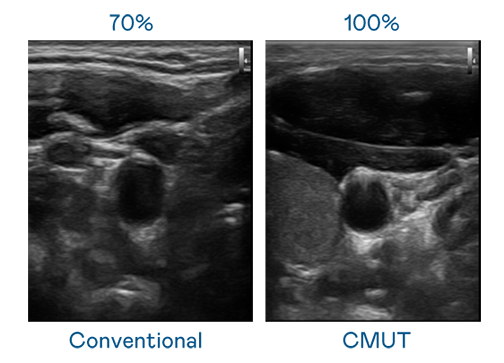

CMUT 技术是一种用电容式微机电元件来产生超音波讯号的技术。与传统 PZT 压电式技术相比,CMUT 频宽增加 30%,更宽频的超音波讯号让影像解析度大幅提升,是实现高影像品质医疗超音波扫描、促进精准医疗发展的关键技术。

大频宽带来超清晰影像

超音波影像的解析度高低,首先取决于探头能发出的讯号频宽。人生就是搏尊龙 CMUT 可提供高清晰的超音波讯号,提供高频宽、高灵敏度、影像纹理细节更高的超音波影像,协助医护人员缩短影像判读时间及利用精准的医疗影像进行诊断。